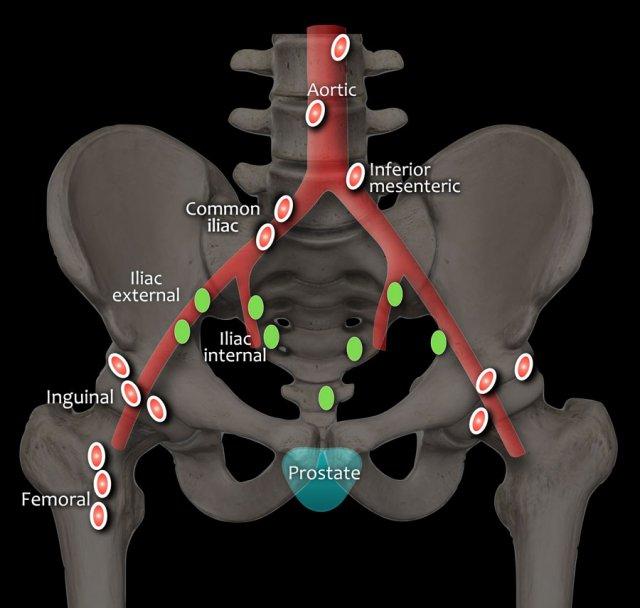

Hạch bạch huyết vùng (màu xanh lá) nằm dưới mức chỗ phân chia động mạch chậu chung và được phân giai đoạn N1:

- Hạch chậu

- Hạch hạ vị

- Hạch cùng

- Hạch chậu (trong, ngoài)

Hạch bạch huyết xa (màu đỏ) nằm ngoài các vùng này và được phân giai đoạn là bệnh di căn M1a:

- Hạch cạnh động mạch chủ

- Hạch chậu chung

- Hạch bẹn

- Hạch thượng đòn